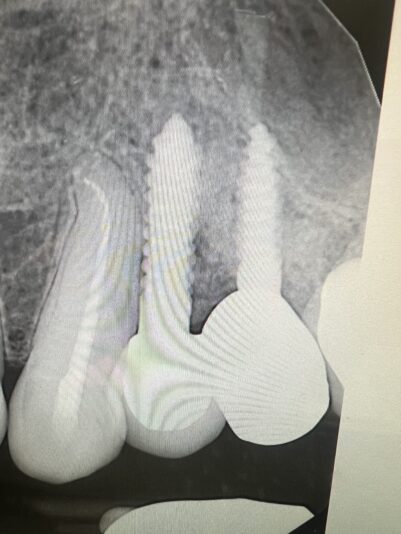

• Reply to Upper Anterior Implant Position

I agree with Ivan that you might have bone there (also agree don’t flap it lol). These things happen and we learn from them!

• Reply to #10 implant site

You are totally right that palatal bone is less likely to get resorption or peri-implantitis and that most problems occur on the buccal. However, as a periodontist I often get cases sent to me where they went too palatal and now there’s no palatal support for the implant. 1.5-2mm buccal and palatal is a recipe for success in my book.